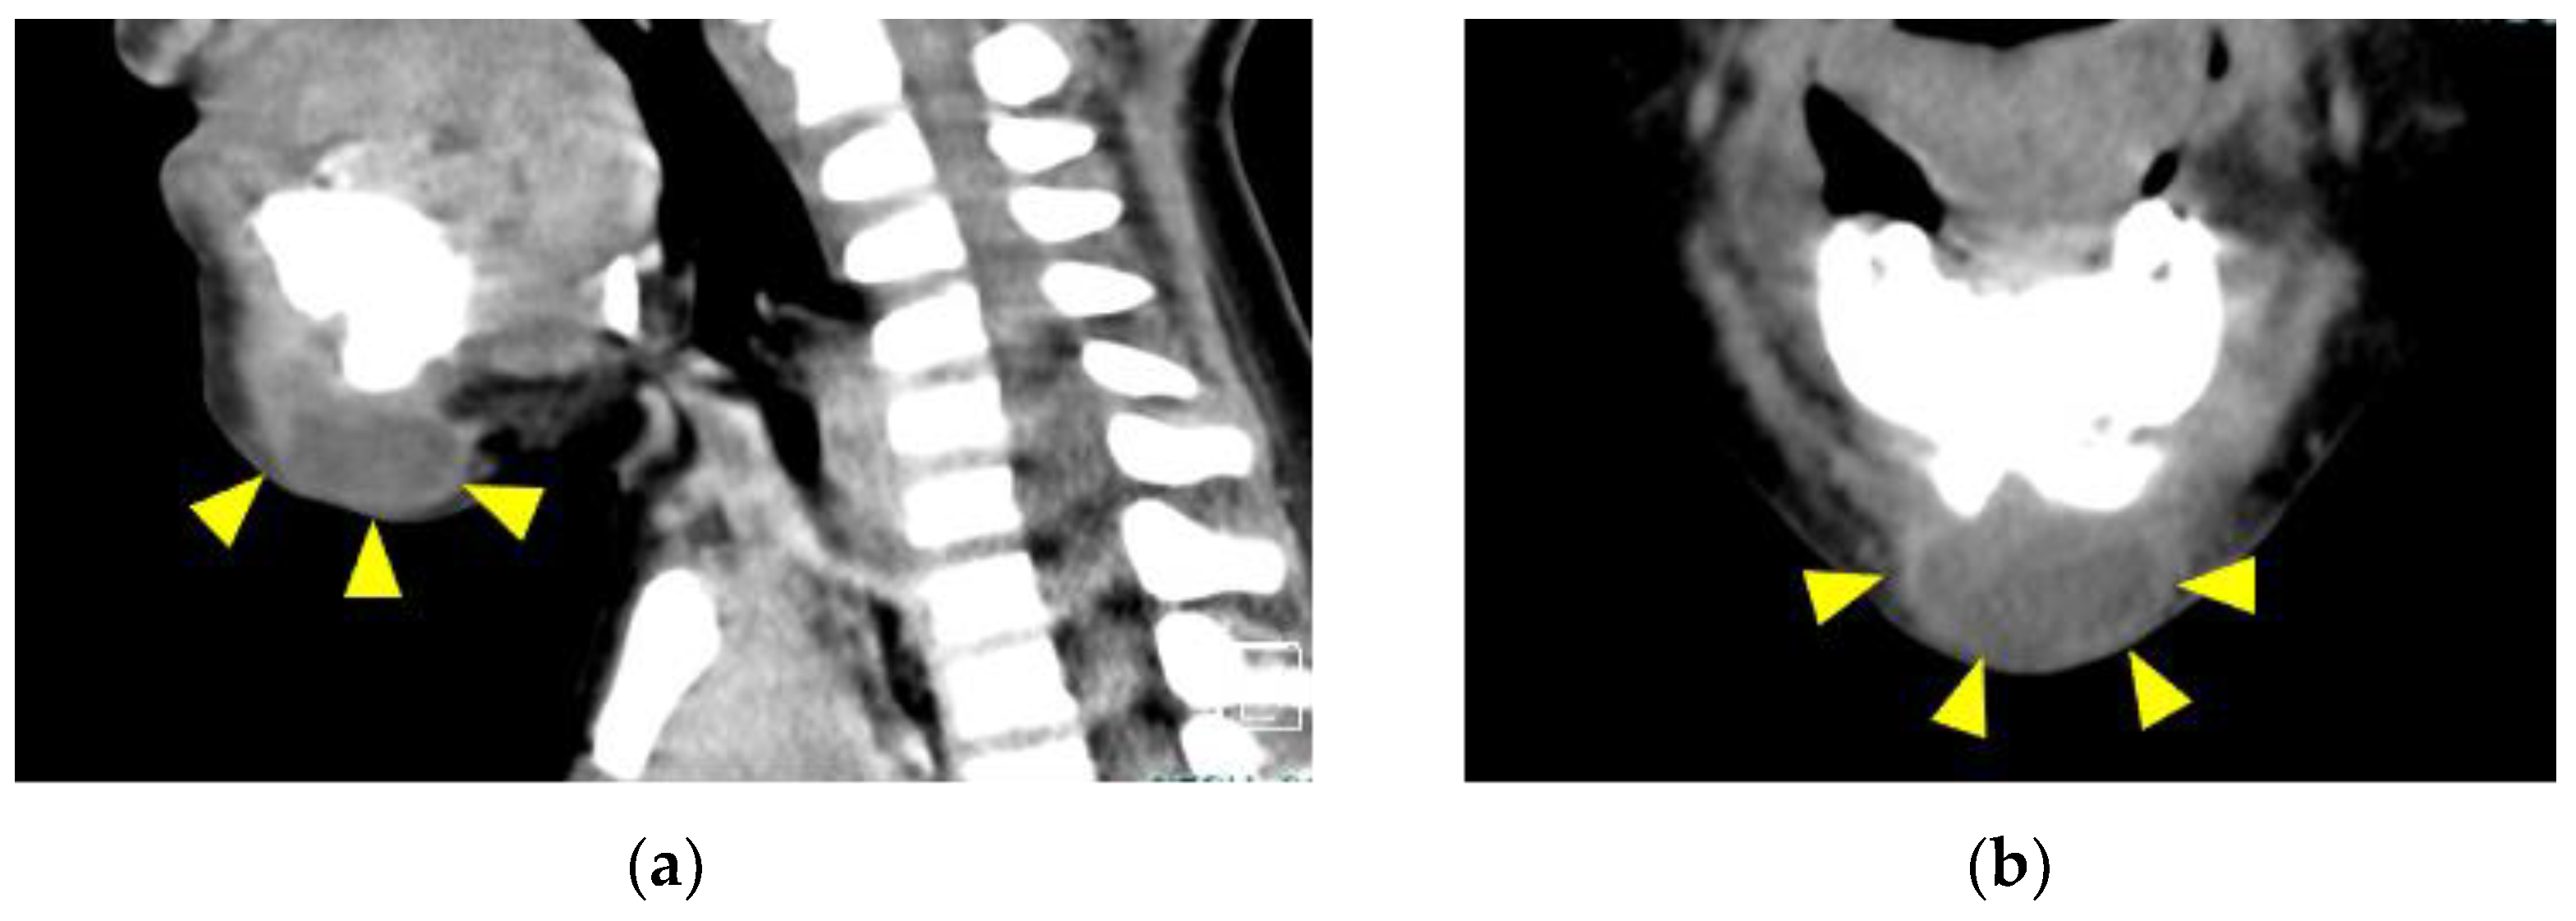

2. Case Presentation